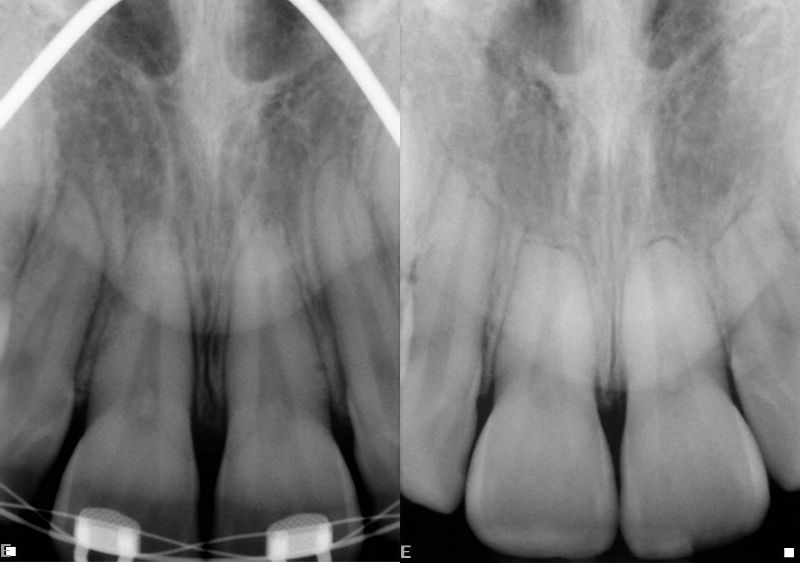

Rotresorption

Resorptionsgrader